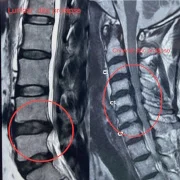

Our hospital offers comprehensive lumbar spine surgery in Thane for lower back problems such as herniated discs, sciatica, lumbar canal stenosis, and degenerative spine disorders. Procedures like laminectomy, lumbar discectomy, or minimally invasive lumbar fusion help patients regain function and reduce pain. With a patient-focused approach, we ensure safe outcomes and faster rehabilitation.

– Disc Prolapse